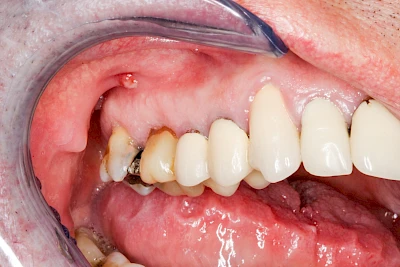

Bei einer Fistel hat sich meist eine Entzündung (manchmal auch Erreger selbst) z. B. aufgrund von Karies oder aufgrund eines Unfalls über den Zahnnerv und die Wurzelspitze (Apex) in den umliegenden Knochen ausgebreitet (apikale Parodontitis) und schnell einen Weg durch den umgebenden Knochen und die aufliegende Schleimhaut in die Mundhöhle gebahnt.

Fisteln sind in der Regel nicht schmerzhaft und fallen häufig als kleine Öffnung weiter entfernt vom Zahnfleisch nahe der Umschlagfalte auf. Aus der Fistelöffnung entleert sich spontan gelbliches Sekret (Eiter) oder es lässt sich mit dem Finger ausstreichen. Manchmal beschreiben die betroffenen Menschen immer wieder einen komischen Geschmack im Mund.

Im fortgeschrittenen Stadium kann die Schleimhaut sich weiter zurückgezogen haben und die Wurzelspitze sichtbar sein. In der Regel treten bei Fisteln keine Schwellungen auf, weil sich die Entzündung nicht im Gewebe ausbreitet.

Bei Fisteln sollte zeitnah der Zahnarzt kontaktiert werden. Treten Fisteln im Zusammenhang mit Schwellungen auf, ist sofort der Zahnarzt zu kontaktieren. Ist der Zahnarzt nicht zu erreichen und es verschlechtert sich der Allgemeinzustand (z. B. Fieber) sollte der Notarzt gerufen werden.